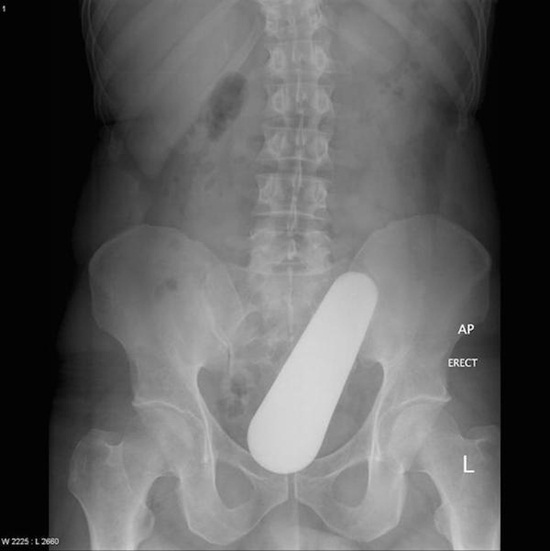

มาดูภาพเอกซเรย์ สารพัดสิ่งของที่เคยหลุดเข้าทวารหนัก

เผยภาพเอกซเรย์สุดอึ้ง สารพัดสิ่งที่เคยหลุดเข้าไปภายในทวารหนักผู้ป่วยทั่วโลก แปลกพิสดารกันจริง ๆ

การยัดสิ่งของต่าง ๆ เข้าไปในทวารหนักนั้น ไม่ว่าจะด้วยเหตุผลเพื่อหลบซ่อนการตรวจของเจ้าหน้าที่ทางการ หรือเป็นความผิดพลาดจากการแก้ขัดเมื่อเกิดอารมณ์ทางเพศก็ตาม สิ่งของที่หลุดเข้าไปนั้นล้วนแล้วแต่สร้างอันตรายให้กับอวัยวะภายในของผู้ป่วยได้หมด แต่ถึงจะเป็นอย่างนั้น เคสทางการแพทย์ว่าด้วยเรื่องของสิ่งแปลกปลอมที่หลุดเข้าไปในทวารหนักก็ยังมีให้เห็นอยู่เรื่อย ๆ ถมเถ แต่ละอย่างทำเอาอึ้ง ทึ่ง แบบไม่คิดว่ามันจะหลุดเข้าไปในทวารหนักได้จริง ๆ ดังเช่นตัวอย่างเคสที่เรานำมาฝากกันในวันนี้..

ไฟฉาย